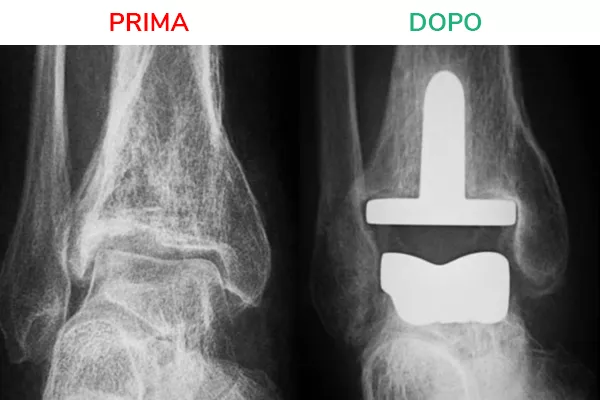

Radiografia in movimento

La radiografia in movimento mostra lo spazio articolare ripristinato e la distanza tra tibia e astragalo. Il movimento risulta fluido e scorrevole, simile a quello fisiologico. Il risultato che si deve ottenere al termine dell’intervento di Protesi di Caviglia è la normale mobilità della caviglia in flesso-estensione.